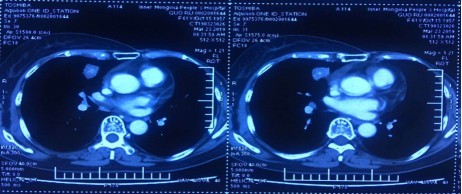

2018年12月,疾病再次进展。转移灶大小:25×27mm。

右肺中叶内侧段结节25×27mm,较前增大纵膈、右肺门多发增大淋巴结

疗效评价:PR。转移灶大小:22×24mm